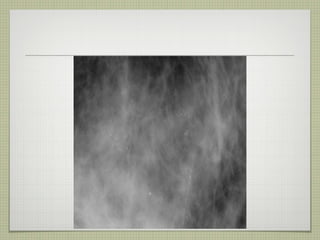

Calcificaciones amorfas birads 2: difusas y bilaterales birads 3: múltiples grupos bilaterales birads 4: grupos unilaterales o de nueva aparición o aumento durante el  seguimiento  o en pacientes con neoplasia de la mama contralateral

Calcificaciones amorfas birads2: difusas y bilaterales birads 3: múltiples grupos bilaterales birads 4: grupos unilaterales o de nueva aparición o aumento durante el seguimiento o en pacientes con neoplasia de la mama contralateral